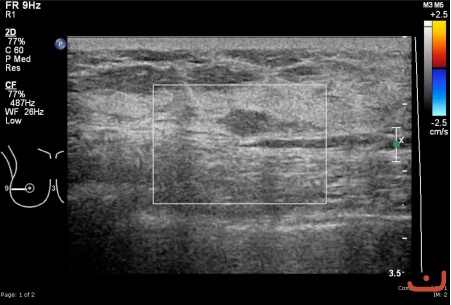

Benign solid mass

Friday, 22 May 2015

99.11 KB (451 x 305 px)